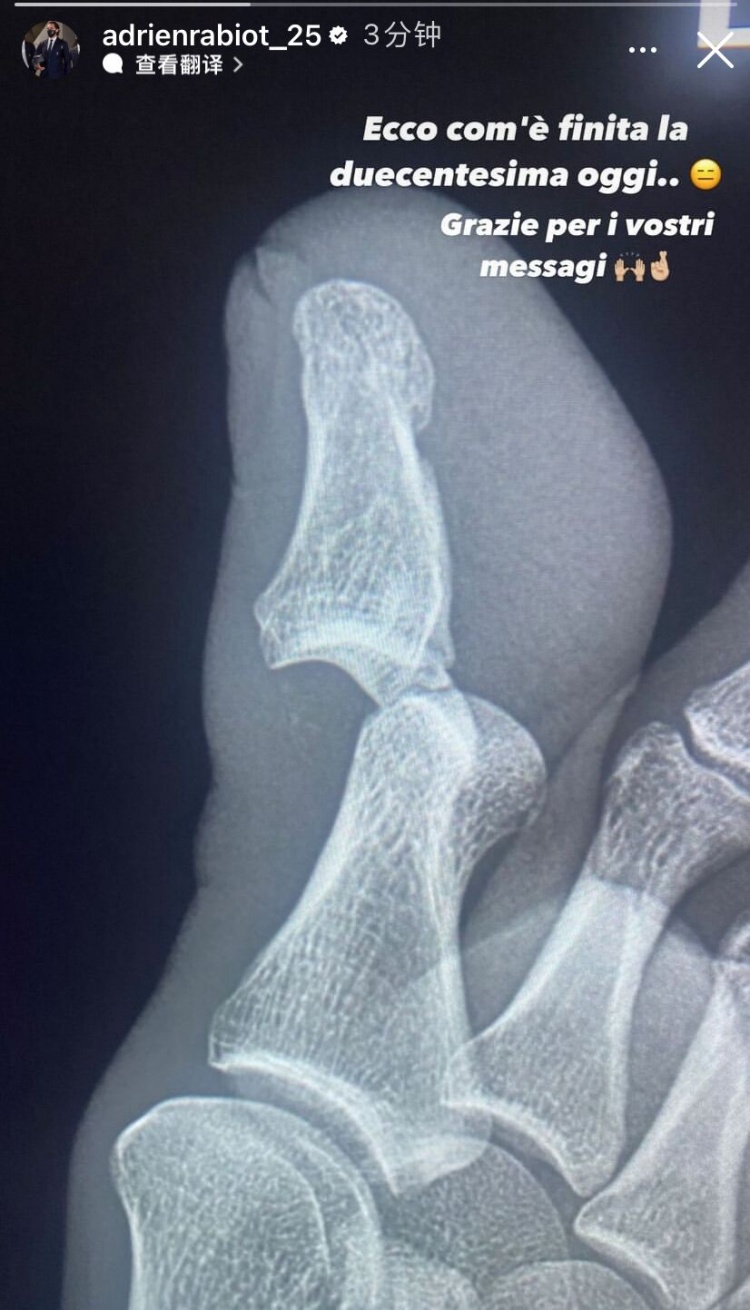

触目惊心!拉比奥特晒脚趾脱臼X光:200场里程碑就这样结束了

赛后,拉比奥特也发出了自己脚趾的X光图片,可以看出脚趾的确严重脱臼。拉比奥特写道:200场里程碑就这样结束了,感谢大家的暖心留言。